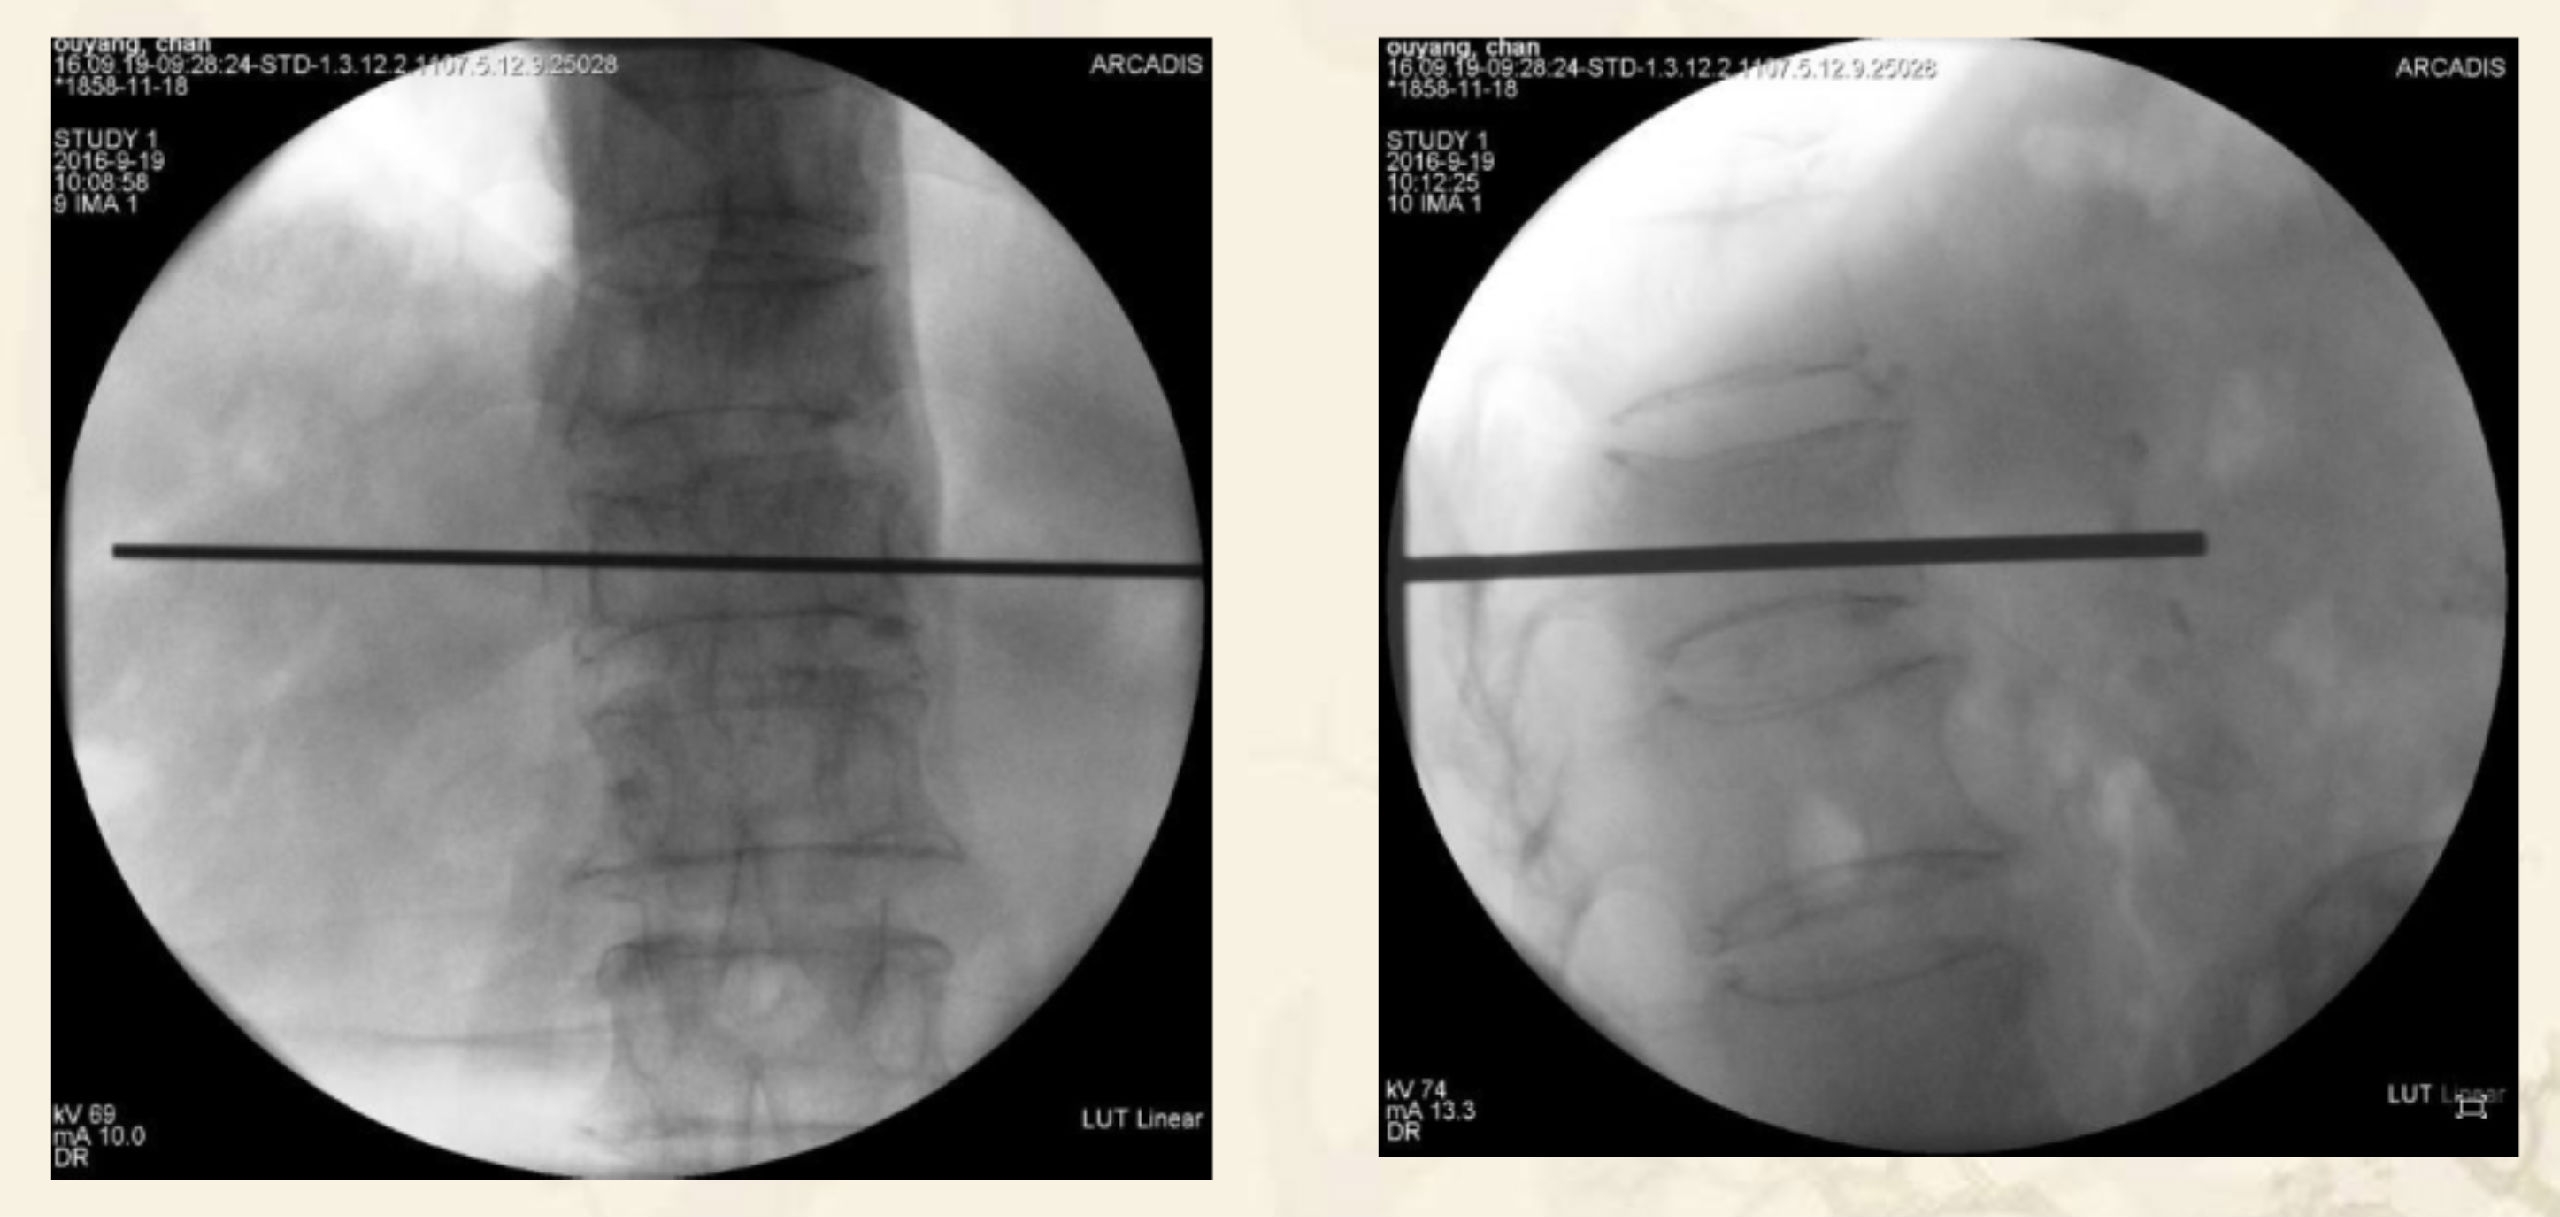

术中透视图

透视引导下,经椎弓根入路或根旁

靶向骨折区置管